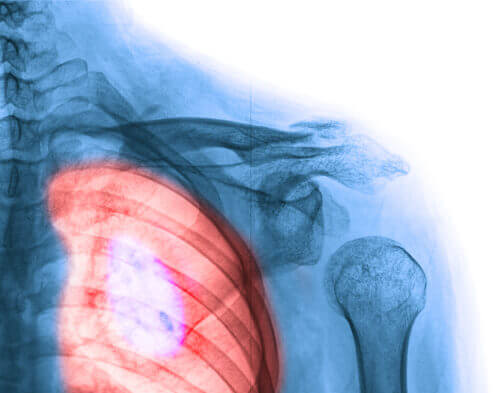

1. Bröstcancer

Bröstcancer är utan tvivel den typ som påverkar kvinnor mest. Vi bör dock nämna något viktigt här: den har högst andel överlevare.

Du känner förmodligen någon som har bröstcancer, eller så har du kanske förlorat en närstående till denna hemska sjukdom. Eftersom vetenskapen gör framsteg varje dag överlever dock fler och fler kvinnor. Att genomföra självundersökningar av sina bröst samt att genomgå mammografi är nyckelfaktorer i att upptäcka bröstcancer. Här följer några tecken och symtom som du ska ha i åtanke:

- En knöl på bröstet, bröstvårtan eller i armhålan som inte var där tidigare.

- Smärta i bröstet när du trycker på det.

- Förändring av bröststorlek.

- Oegentligheter på huden: förändring av färg, sår, eller en textur som liknar apelsinskal.